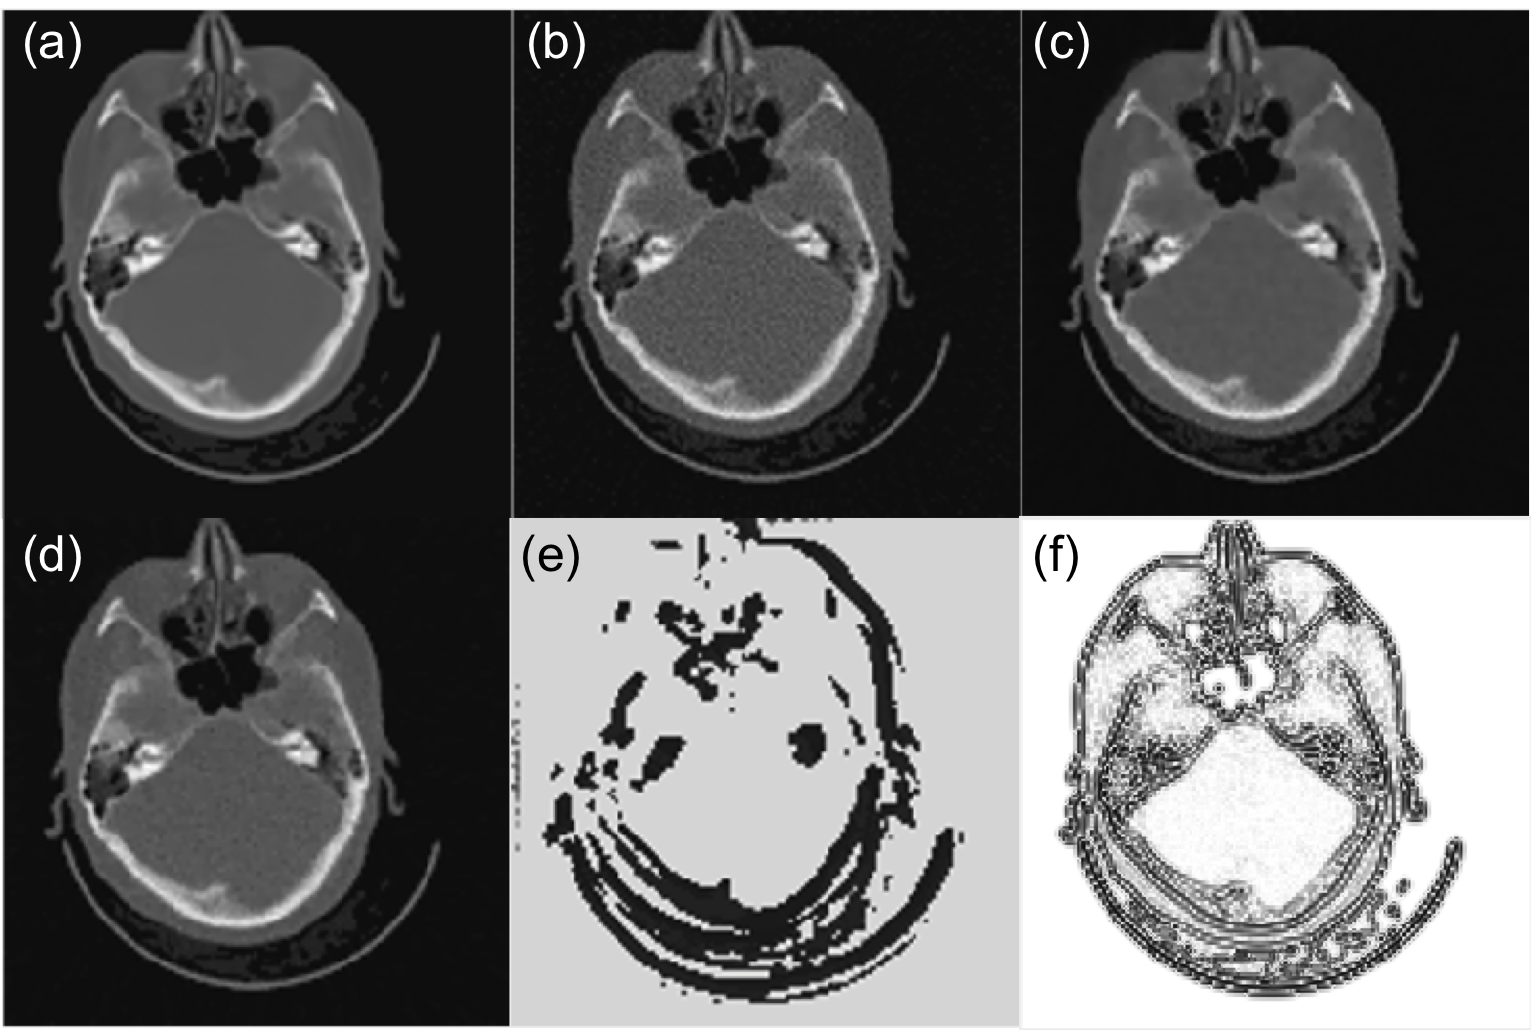

To observe this process in detail, we select a test case that is not used in training. Fig. 5(a)-(c) present reconstructed CT images at step 1, 4, and 7. It is clear that the image quality is improved with the parameter tuned. Quantitatively, we compute the relative error e=|ff|/|f|𝑒𝑓superscript𝑓superscript𝑓e=|f-f^{*}|/|f^{*}| at different steps and plot it in Fig. 5(d). A monotonic decay trend is observed, indicating the effectiveness of parameter tuning.

Figure 5: (a)-(c) Reconstructed images at step 1, 4, and 7. (d) Error e(%)e(\%) as a function of parameter tuning step.

III-B2 Reconstruction results

Fig. 6 is a case that is used in training, whereas Fig. 7 is the same one in Fig. 5, which is not included in training. Since we arbitrarily set initial values of λ(x)𝜆𝑥\lambda(x), which is too small in these two cases, the resulting images contain a lot of noise (Fig. 6(b) and 7(b)). After the parameter λ(x)𝜆𝑥\lambda(x) is tuned by PTPN, the image quality in both cases is substantially improved (Fig. 6(c) and 7(c)).

We compare the results with those under manually tuned parameters. Since it is impractical for one to adjust the parameter for each individual pixel, we consider a special context that the parameter is a constant throughout the image and we manually adjust this parameter value for the best image quality. The appropriate parameter values are λ(x)=0.05𝜆𝑥0.05\lambda(x)=0.05 for Fig. 6 and λ(x)=0.12𝜆𝑥0.12\lambda(x)=0.12 for Fig. 7. Fig. 6(d) and 7(d) depict images reconstructed under these parameters in the two cases, respectively. It is found that the images still contain a certain amount of noise and the quality is inferior to those with parameters tuned by PTPN.

Refer to caption

Figure 6: (a) Ground truth CT image of a case that is used in training PTPN. (b) Image reconstructed with an arbitrarily selected parameter λ(x)=0.005𝜆𝑥0.005\lambda(x)=0.005. (c) Image reconstructed after the parameter is tuned by PTPN. (d) Image reconstructed by manually tuned to λ(x)=0.05𝜆𝑥0.05\lambda(x)=0.05. (e) Tuned parameter map λ(x)𝜆𝑥\lambda(x). (e) Optimal parameter map λ(x)superscript𝜆𝑥\lambda^{*}(x).

As for the parameter maps tuned by the PTPN shown in Fig. 6(e) and 7(e), it is observed that PTPN deliberately reduces parameter values most around image edges. This is understandable. Reducing parameters at those pixels decreases the amount of regularization in those areas, which is beneficial in terms of preserving image edges.

Interestingly, for the simple problem in Eq. (2), it is possible to derive the optimal parameter map λ(x)superscript𝜆𝑥\lambda^{*}(x). As such, let us take the gradient of the objective function and set it to zero at f=f𝑓superscript𝑓f=f^{*}: PT(Pfg)λ(f|f|)|f=f=0superscript𝑃𝑇𝑃𝑓𝑔evaluated-at𝜆𝑓𝑓𝑓superscript𝑓0\left.P^{T}(Pf-g)-\lambda\nabla\cdot\left(\frac{\nabla f}{|\nabla f|}\right)\right|_{f=f^{*}}=0. This implies that the optimal parameter map is

The numerator in this expression is more or less an image of noise that is obtained by back-projecting the residual error in the projection domain to the image domain. Here, we neglect the image structure of the noise and plot the image 1/(f|f|)1superscript𝑓superscript𝑓1/\nabla\cdot\left(\frac{\nabla f^{*}}{|\nabla f^{*}|}\right) in Fig. 6(f) and 7(f) for the two cases, respectively. The images shows that λ(x)superscript𝜆𝑥\lambda^{*}(x) is small along the image edges. Comparing subfigures (e) and (f) in Fig. 6 and Fig. 7, the similarity between corresponding pair of images implies that PTPN can intelligently adjust λ(x)𝜆𝑥\lambda(x) towards the optimal parameter maps. Note that this intelligence is purely developed by the PTPN itself through the reinforcement learning process. Except providing rewards for an action, we do not explicitly give any information regarding how to tune the parameters.